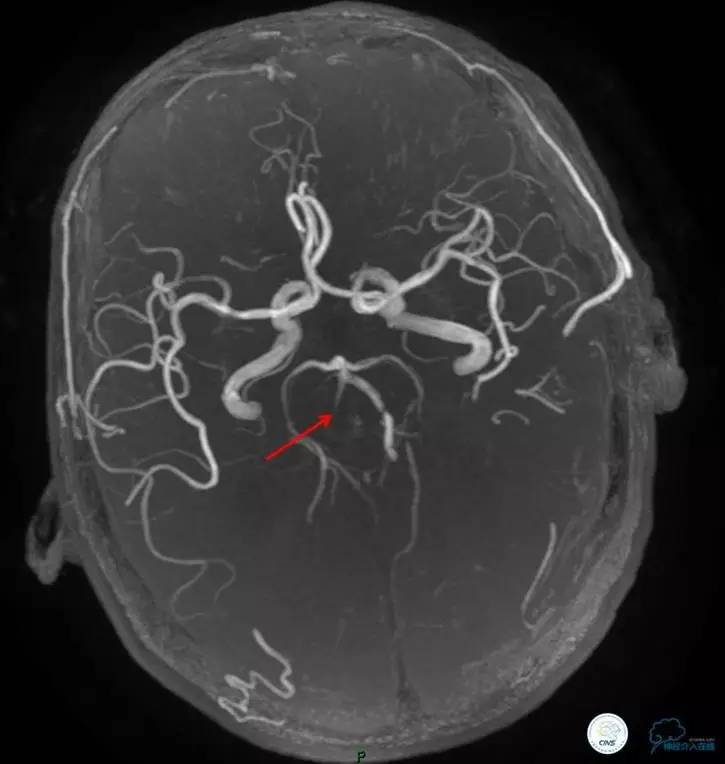

术前DSA

▼2013-12-13